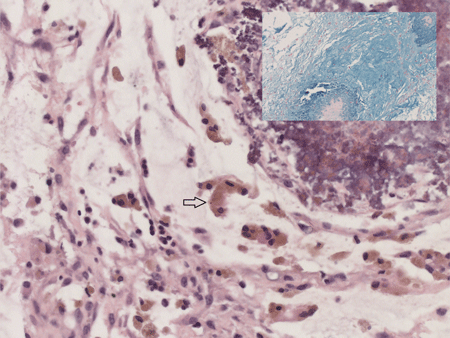

At 6 weeks of age she was referred to us with bilateral incarcerated inguinal hernias. She had no evidence of bowel obstruction and clinically there were firm masses on both groins suggesting ovary as the most likely content. Bilateral inguinal herniotomy was carried out promptly. However, Intra-operatively on either side the inguinal hernial sacs contained omentum attached to an irregular, grey coloured mass with nodules distally. This mass was excised, healthy omentum returned and a standard herniotomy carried out on both sides. Post-operatively she recovered well and was discharged the following day. Histopathological examination confirmed the excised mass to be made up of omentum with areas of dystrophic calcification reminiscent of the saponification with mucin and meconium-laden macrophages; consistent with antenatal perforation of intestine (Fig. 1). At 3 months of follow-up, she remains well and opening her bowels regularly.

Figure 1: Histological images of omental mass excised during inguinal herniotomy in our patient displaying omentum with meconium-laden macrophages (arrow), Haemotoxylin and Eosin stain, magnification X40; [Inset displaying mucin, stained with Alcian blue, magnification X10] |